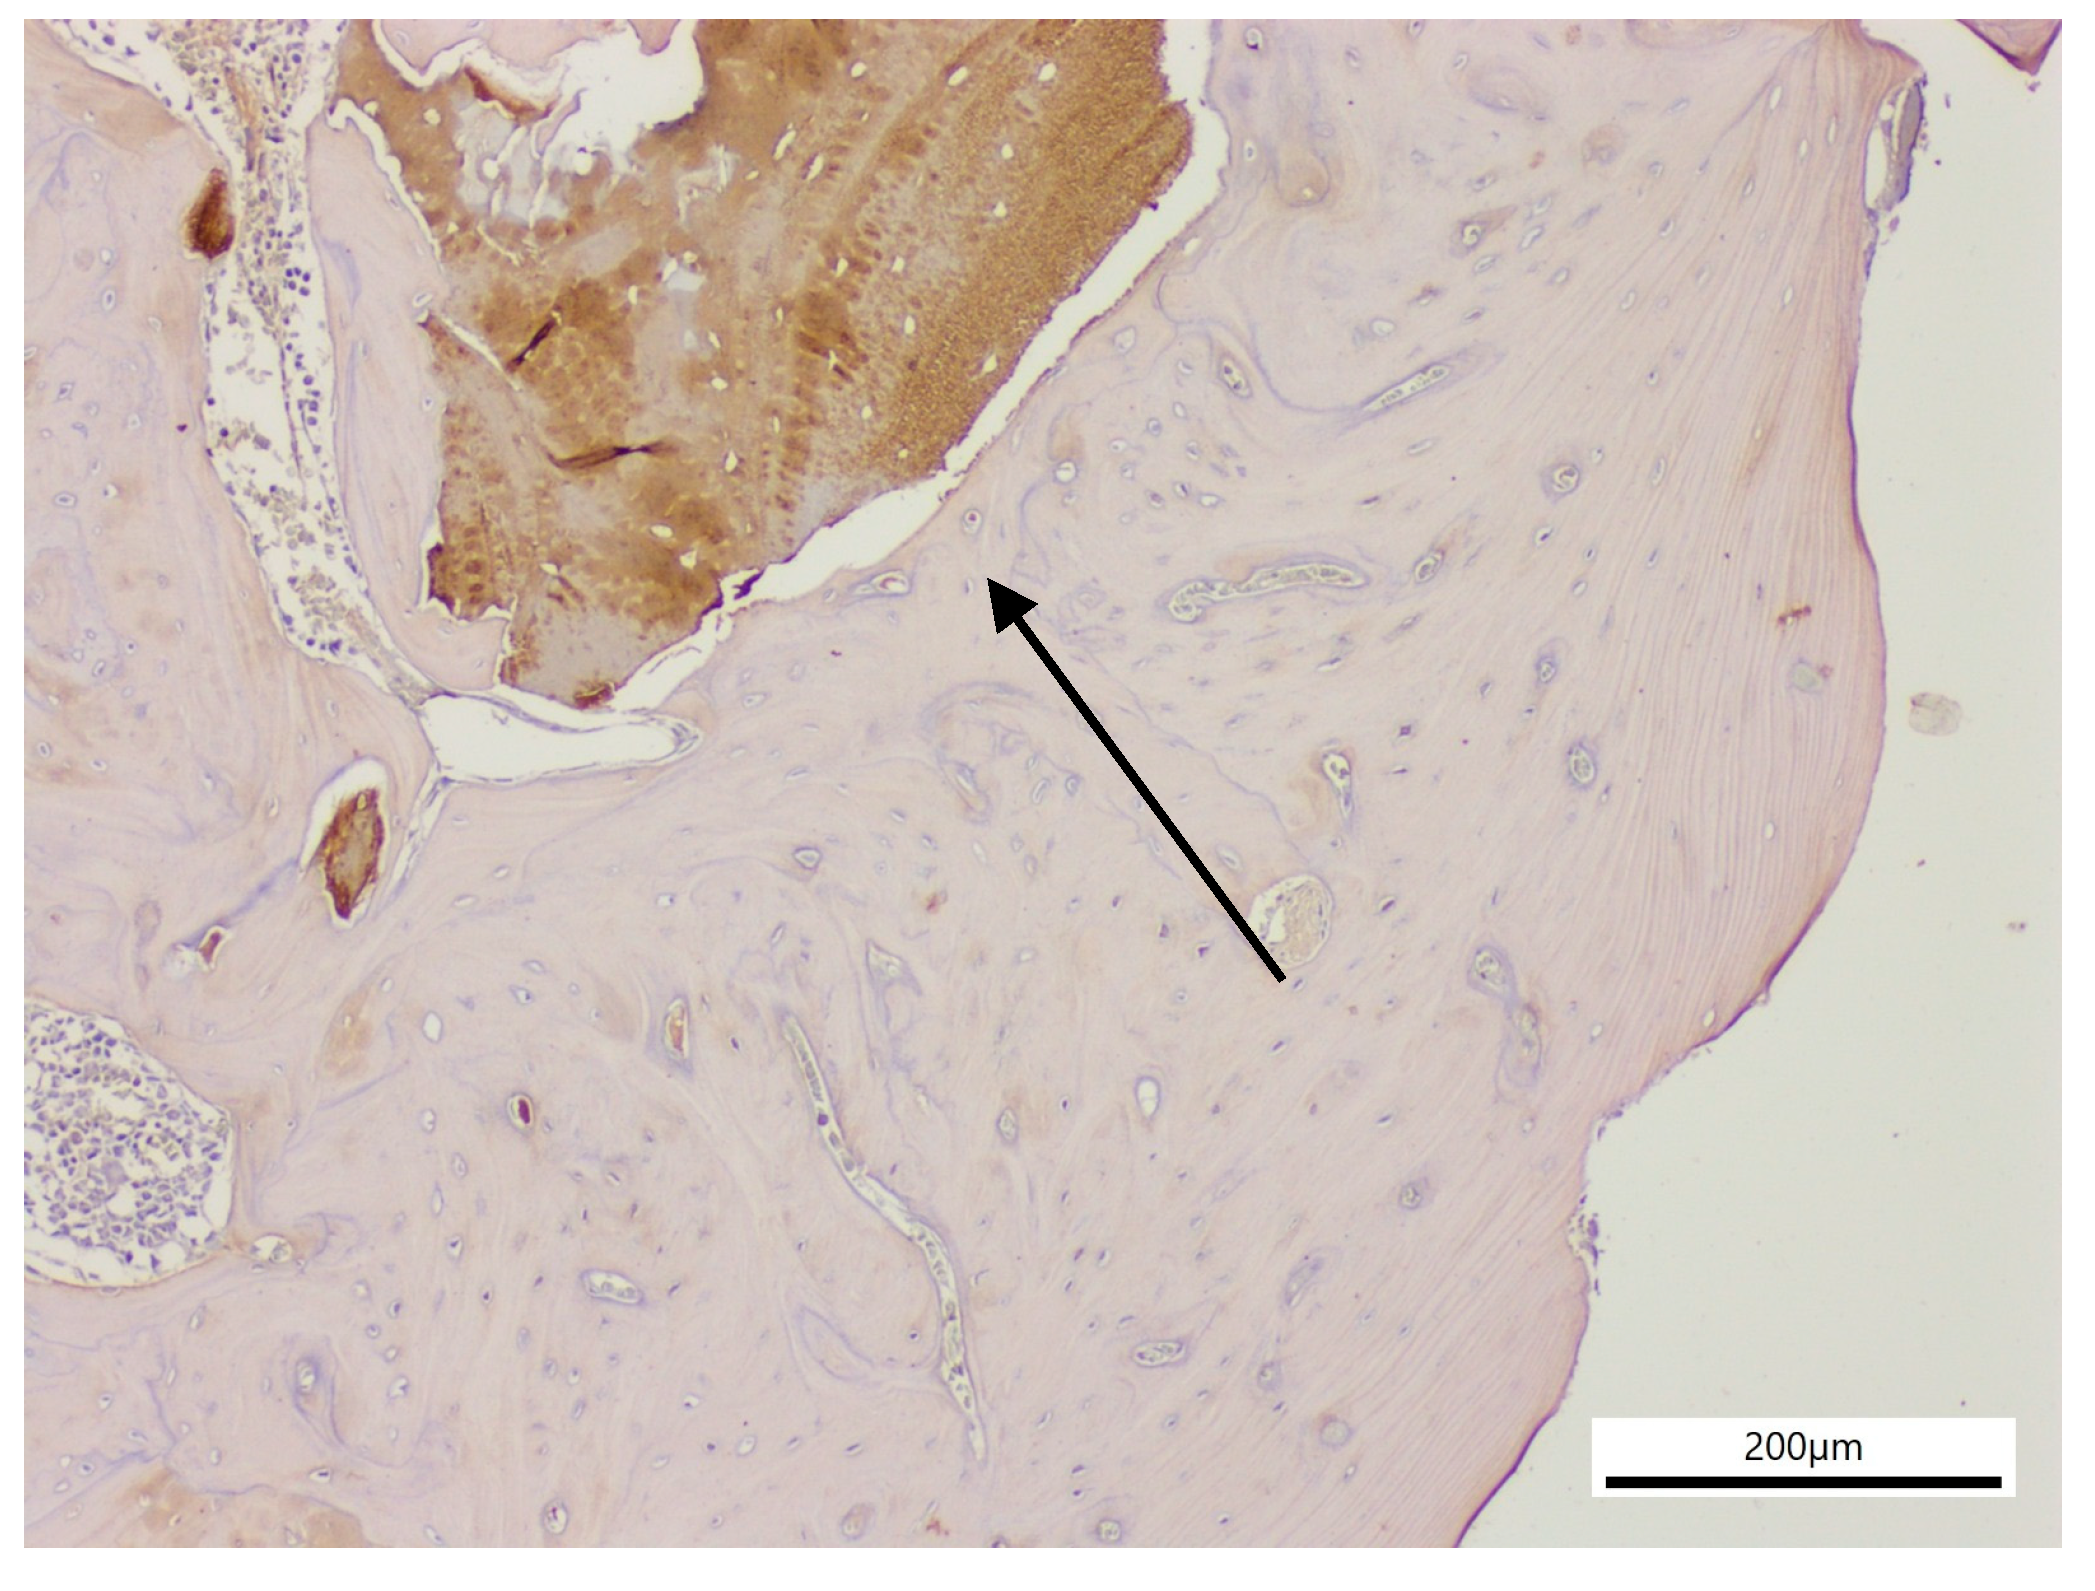

2.5. Histochemical Staining

2.6. Immunohistochemical Analysis